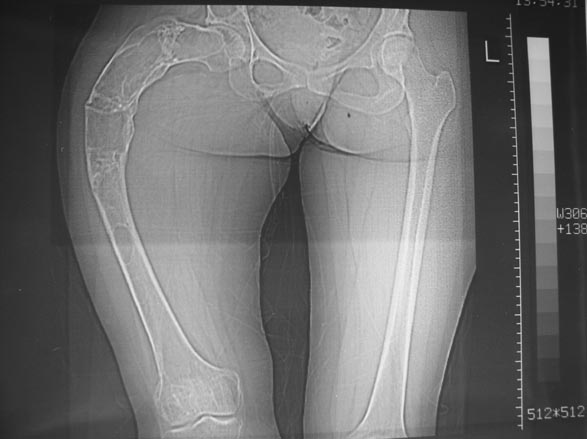

Женщина 28 лет, Больна с 12 летнего возраста, Когда после адекватной травмы получила перелом бедра. На рентгенограммах выявлено какое-то (рентгенограмм и документов нет) изменение бедренной кости, была оперирована, имеется гистологическое заключение - фиброзная дисплазия.дСформировалась деформация бедра. На сегодня - Укорочение 7см. Грубая деформация бедра по типу "пастушьей палки", последний патологический перелом в январе 2004г., консолидировавшийся при консервативном лечении. Имеются грубые изменения и в надвертлужном массиве.-- С уважением, Leonid

Собственно сустав не беспокоит, объем движений полный. По скиаграммам получается, что достаточно одной остеотомии на вершине деформации, чтобы восстановить длину и вывести коленный сустав в нужное положение.

Подобная дефомация может быть исправлена только при помощи КДО аппаратов с клиновивной резекцией бедренной кости + исправление ротационного компонента.

Т\б сустав явно патологичен. Но лечение патологии т\б сутава можно оставить на будущее.

На мой взгляд, для того, чтобы правильно исправить данную деформацию, необходимо обследование больного, которое должно включить в себя, помимо осмотра: 1. Рентгенограммы ( передне-задние и боковые)нижних конечностей на всю длину стоя . 2. Компьютерная томография для измерения длины нижних конечностей. 3. Комьютерная томография тазобедоенных, коленных и голеностопных суставов для измерения углов антеверсии тазобедренных суставов и ротации голеней. Это тот минимум, который должен входить в предоперационное обследование каждого больного с тяжёлыми формами деформаций конечностей.

Поскольку в данном случае имеется дело с довольно большой деформацией с укорочением, одномоментная её устранение с внутренней фиксацией, чревато с одной стороны неправильной коррекцией, с другой, нейроваскулярными осложнениями.

Моё мнение, что двойная остеотомия бедра с аппаратом Илизарова + Гексаподный механизм, или Тэйлора, В данной ситуации является методом выбора. Я очень извеняюсь за качество прилагаемых снимков, в которых я постарался отразить разницу междe одной и двумя остеотомиями бедра.